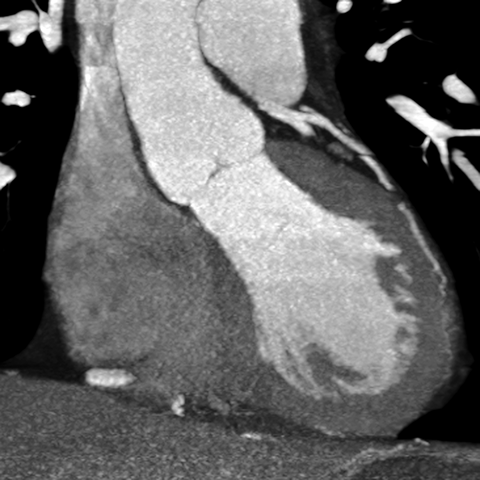

Aortic Valve (CT) [2 of 5]